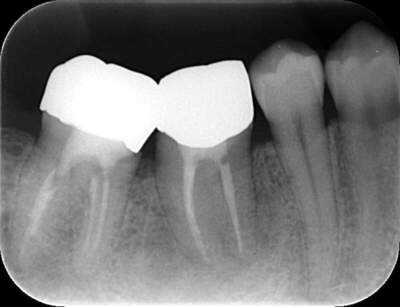

2022.7.9 経過観察後

口腔内写真

レントゲン写真

根管治療後3ヶ月です。根のまわりの骨がやや白くなってきているのがわかります。だんだん骨の添加がみられている証拠になります。

ここまで治癒していればかぶせ物をかぶせても問題ないと判断しました。

2022.8.13 クラウンセット

2022.10.16 予後経過

1年後 2023.3 予後経過

移植した歯はしっかり機能しており、問題なく使用できているとのことである。

最後のレントゲンでは、骨がしっかり添加され、周囲組織となんら変色ない状態にまでなっていることがわかる。